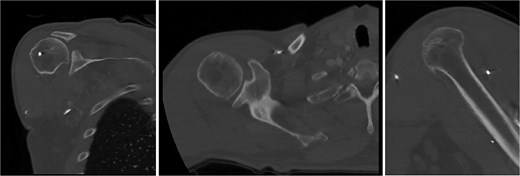

Both shoulders were reduced urgently by the orthopedic team, with immediate improvement in paresthesias (Fig. 2). Post-reduction CTs were significant for bilateral chronic rotator cuff disease with superior migration of the humeral heads, right-sided supraspinatus and subscapularis atrophy, and a left nondisplaced glenoid fracture (Figs 3 and 4). He was discharged home in bilateral slings.

Post-reduction CT of the left shoulder demonstrating superior humeral head migration relative to the glenoid.